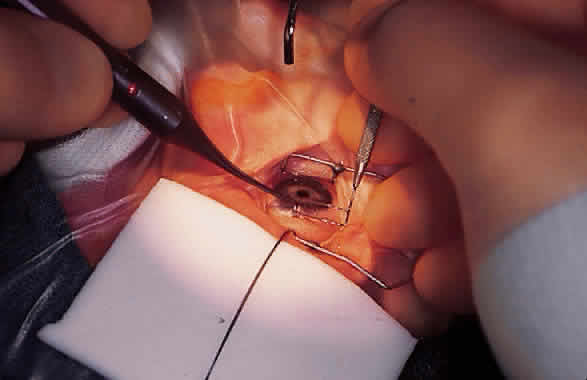

Funduscopy is essential, with both a direct and an indirect ophthalmoscope. The Richardson or Koeppe diagnostic gonioscopy lenses can be of great assistance (Fig. 3). The lens is placed, and then direct ophthalmoscopy is performed through the lens. After this, the periphery should be carefully evaluated with an indirect ophthalmoscope.

Gonioscopy is a mandatory part of the examination under anesthesia. It allows the surgeon to identify the underlying congenital or juvenile glaucoma diagnosis and permits appropriate surgical planning. The Koeppe gonioscopic lens, introduced in 1919,26 has significant advantages over the Zeiss four-mirror or Goldmann three-mirror gonioprism. Chief among these is the ability to compare simultaneously the gonioscopic appearance of two eyes in the same patient (see Fig. 3). The surgeon should be familiar with the gonioscopic findings in primary congenital glaucoma as well as the various secondary glaucomas seen in childhood. Gonioscopic photography can help document the appearance of the anterior chamber angle before and after treatment.